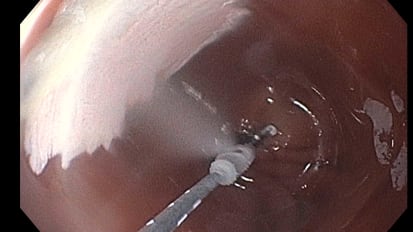

Gastroenterologist Develops Gel to Stop Bleeding After Precancerous Polyp Removal

Venkata Akshintala leads a team of pharmacologists, biomedical engineers and mechanical engineers to create a gel that uses epinephrine nanoparticles to stop bleeding following a procedure.